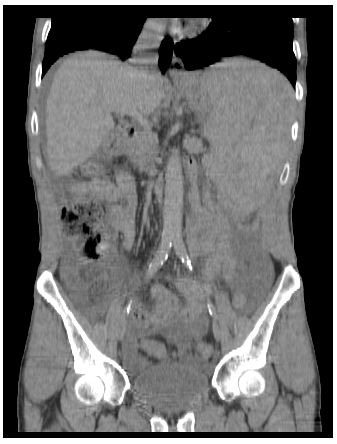

Spontaneous Rupture of the Spleen in the Context of Non-Hodgkin Lymphoma: A Rare Case Report